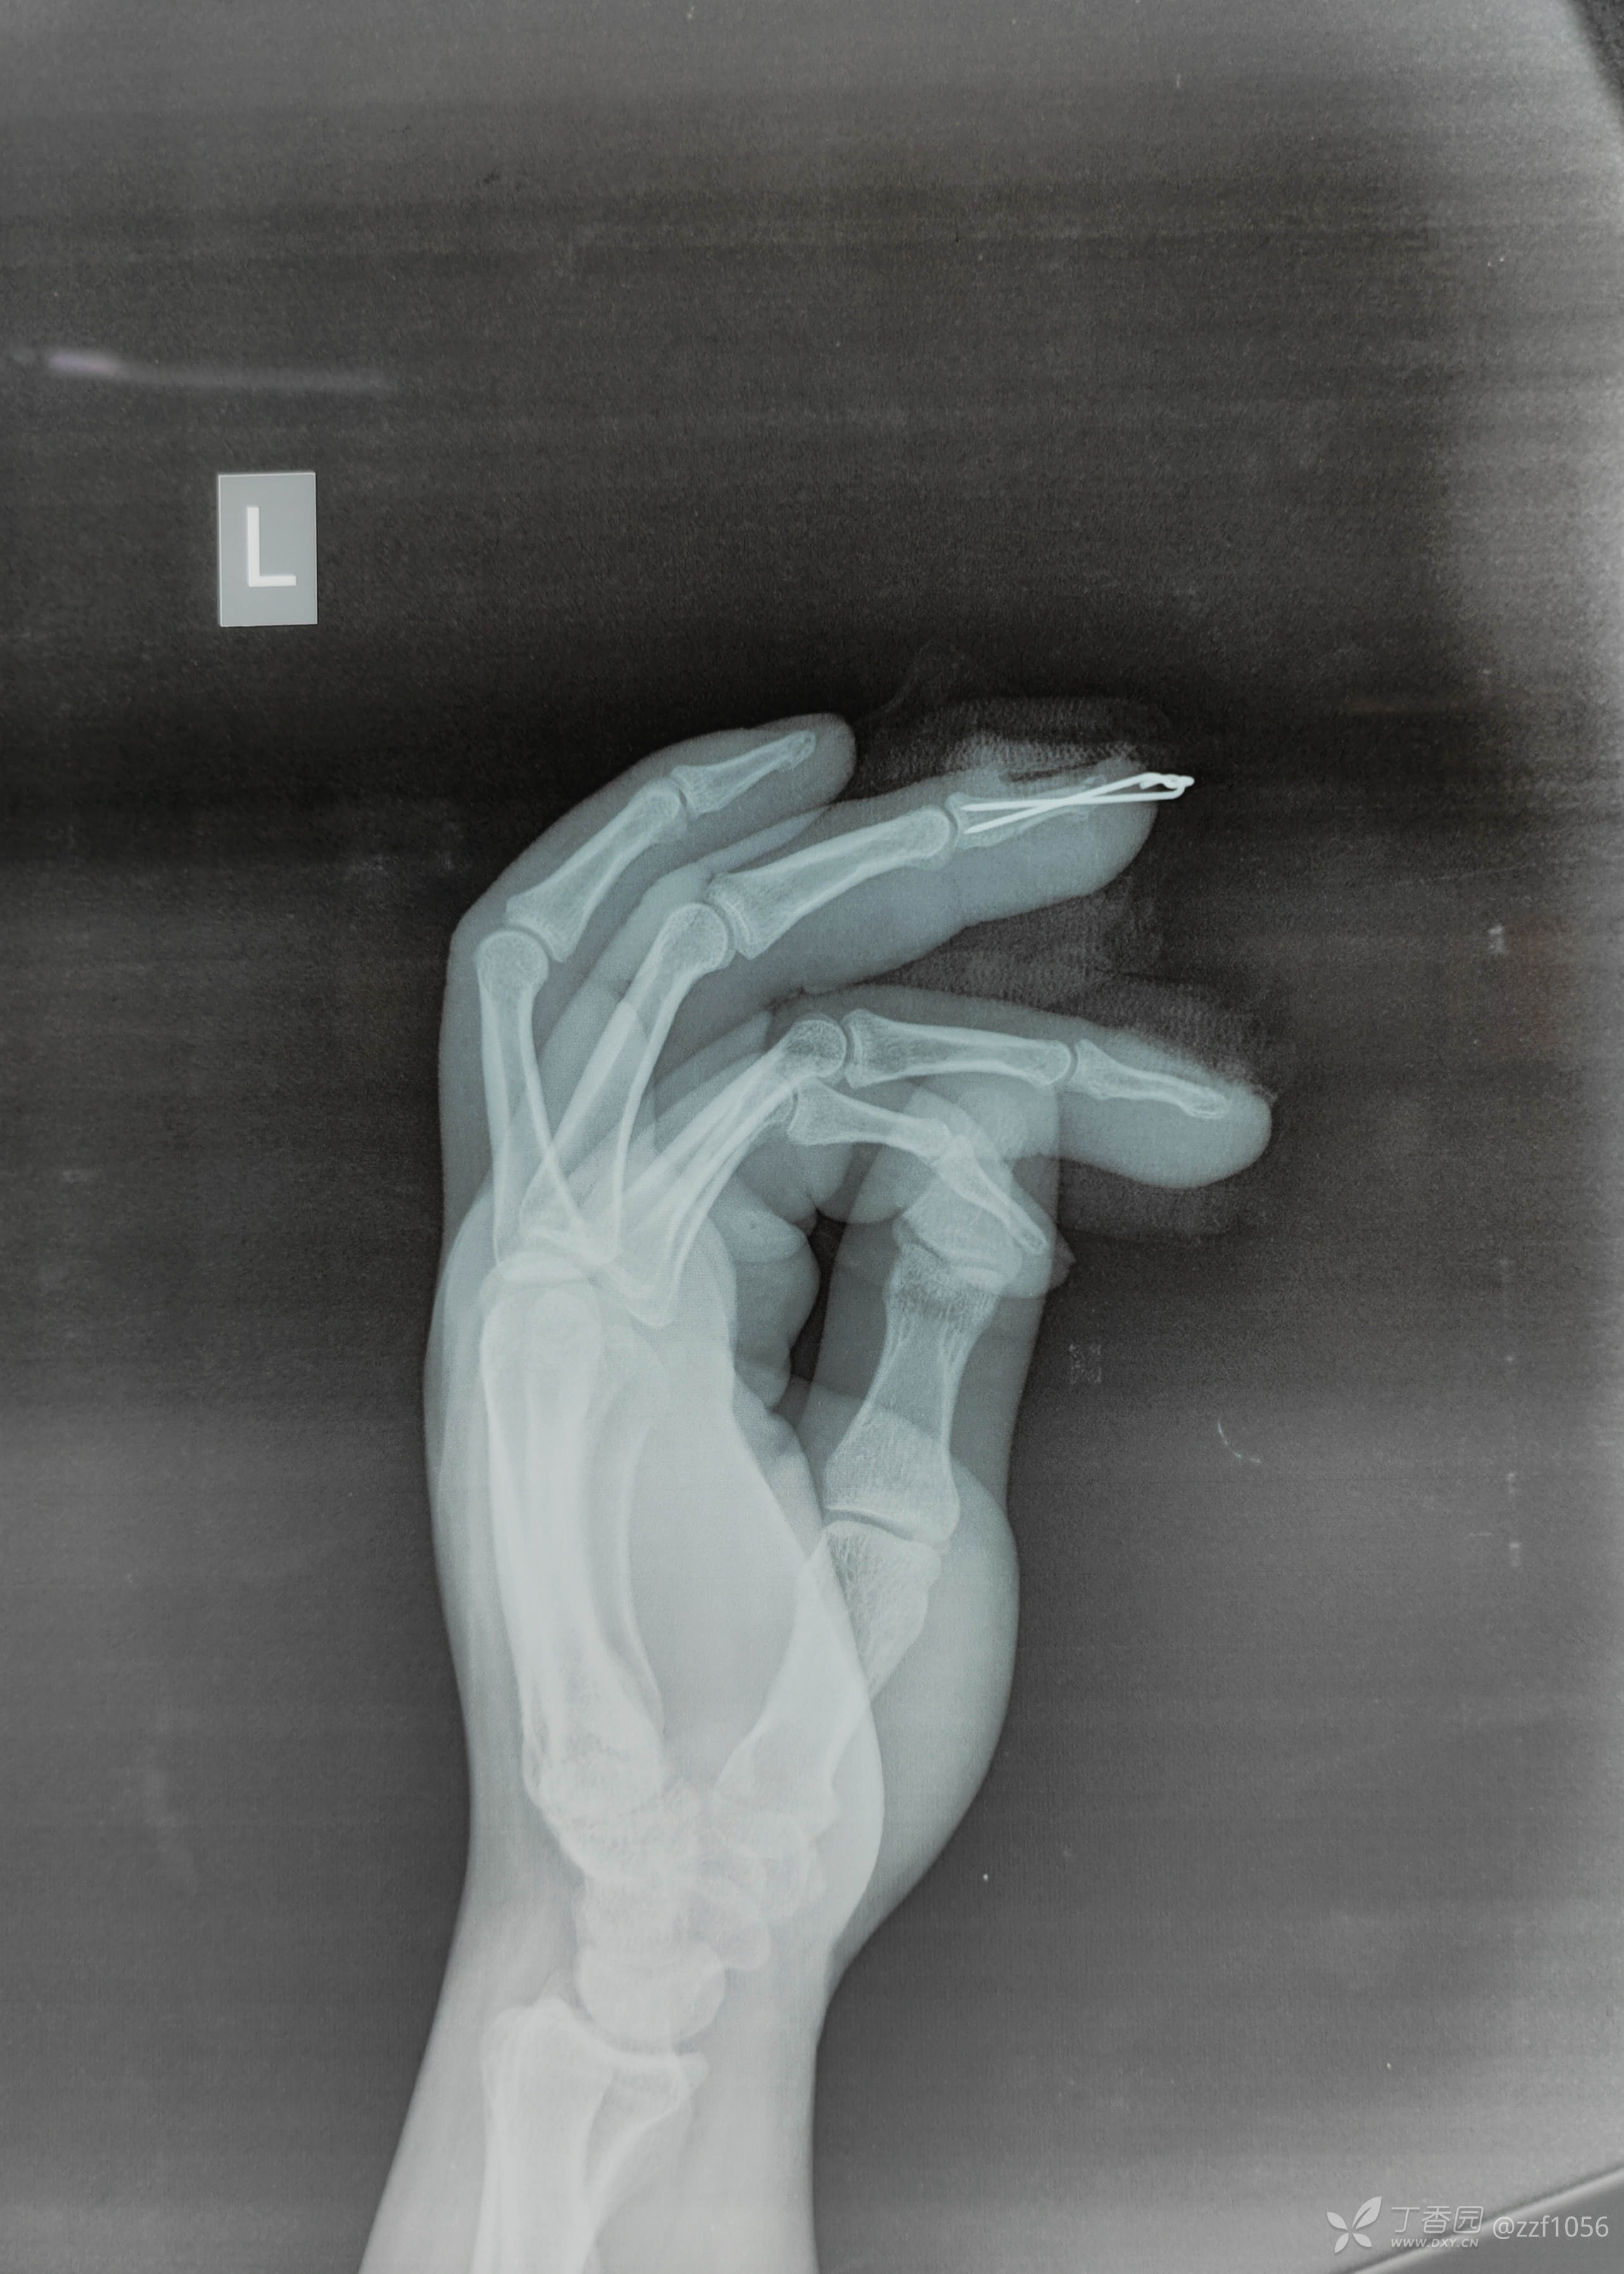

甲床根部破裂嵌入折端,清理后撬拨复位,怎么固定?克氏针一枚还是两枚?纵行还是交叉?需要外固定吗?

指甲是否需要回植?回植的优势?回植的技巧?回植后就安全吗?回植的必要性?